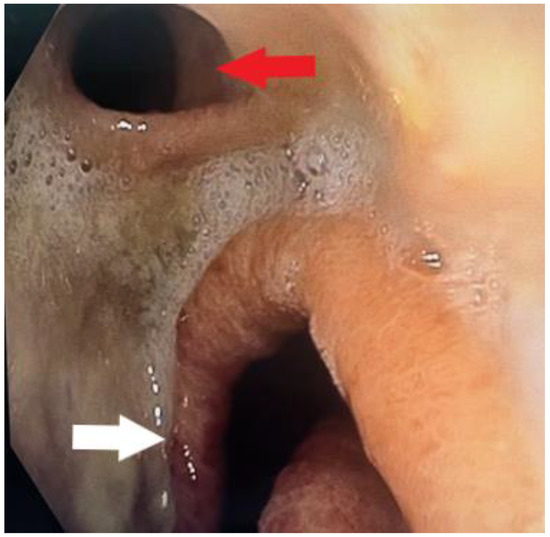

After the resolution of pneumonia, we evaluated the patient. Due to the size and localization of the fistula, no conservative management was possible, and we decided to move forward with the surgical repair of the fistula. Surgery was performed via a right posterolateral thoracotomy, and the gastric tube was disconnected from the esophagus, exposing a defect on the left main bronchus that was 18 mm in diameter. At this time, the patient was very thin; thus, there was no possibility of using the intercostal muscle flap to cover the defect. We decided on the only possible solution: using the posterior wall of the esophagus, proximal to the anastomosis. The esophagus was transected in such a manner that a posterior mucosal flap was created, which was 4 cm long and received a blood supply coming from the posterior esophageal wall (Figure 3). The flap was well vascularized and long enough. We covered the defect with the flap using absorbable 4.0 sutures. An air leak test was performed, showing no leak from the repaired fistula. The procedure was finished with a left cervicotomy and esophagostomy, as well as a median laparotomy and gastrostomy, which were performed on the partially resected gastric tube previously repositioned into the abdomen.

Figure 3.

Intraoperative image showing a defect on the left main bronchus (black arrow) and the esophageal flap prepared for suturing (white arrow). This image was taken after the gastric tube had been disconnected and the esophageal flap prepared. The surrounding tissue was fibrotic. The esophageal flap was well vascularized and had sufficient length.